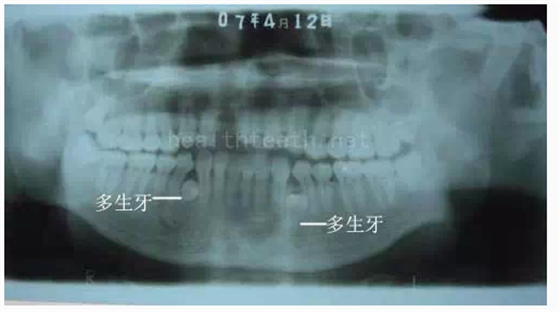

病例3,同時多生兩顆牙齒

QQ圖片20150722094417.png